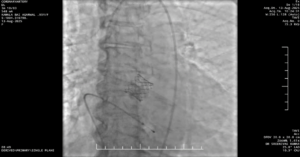

TAVR — A Life-Saving Procedure for a 95-Year-Old

Given her advanced age, open heart surgery was extremely high-risk.

After evaluation by the Heart Team, TAVR offered the safest and most effective solution.

Procedure Details

-

Date: 13/08/2025

Valve: Edwards Sapien 3 Ultra 20 mm

Performed at: Apollo Hospitals, Jubilee Hills

Outcome: Procedure highly successful and uneventful